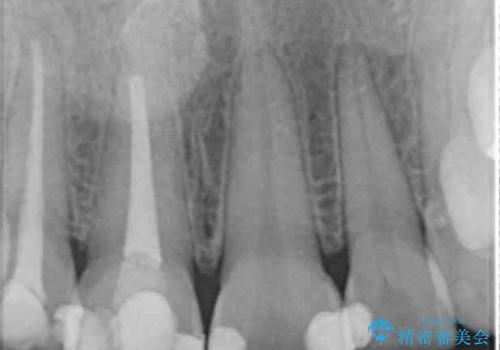

- 前歯が徐々に神経の治療を行ってから変色し、審美性の回復を求めて来院されました。

根尖に病変は見られず、根管治療は行わずに仮歯・ジルコニアクラウンを作製、装着することで審美性を回復しました。